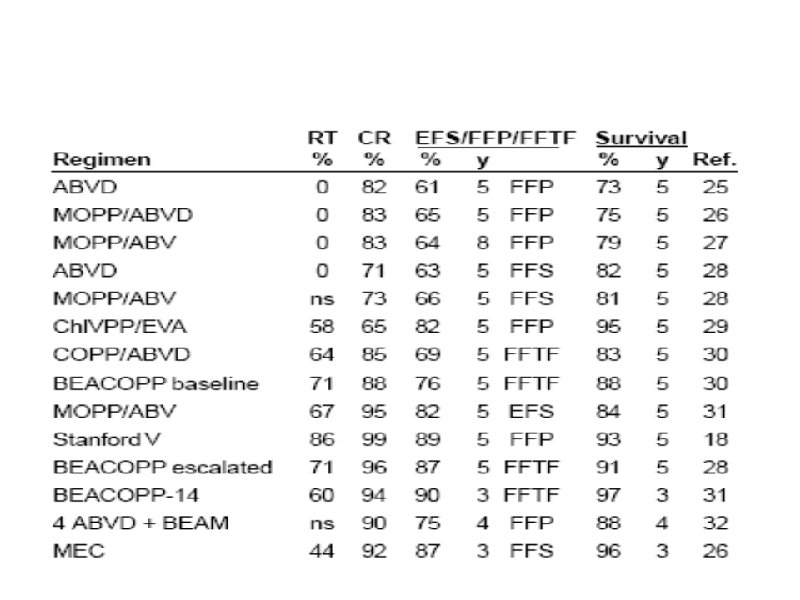

Схемы химиотерапии лимфогрануломатоза